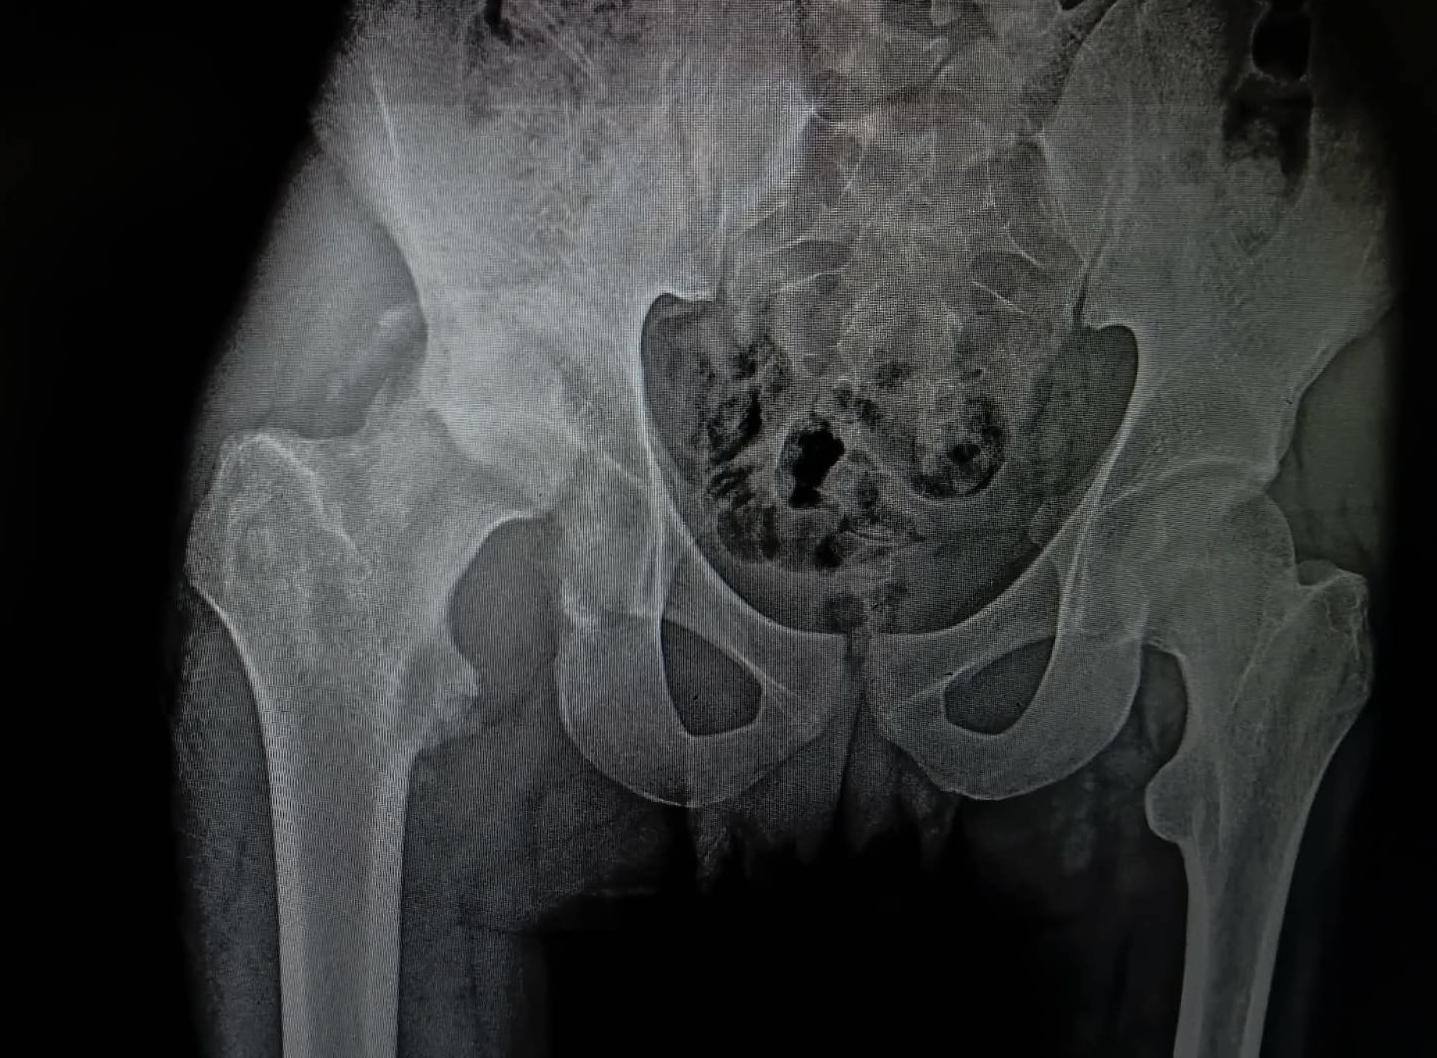

أ.د/ حسام الدين جاد – رئيس قسم جراحة العظام نجحت وحدة جراحات الحوض المتقدمة بقسم جراحة العظام والكسور في إجراء عملية معقدة لرد وتثبيت كسر مهمل بالجدار الخلفى للحق الحرقفى مع وجود خلع مهمل بالمفصل وتحرير العصب الوركى حيث انه حضر إلينا المريض يعانى من آلام فى الحوض وسقوط جزئى بالقدم بعد مرور شهرين من إصابته فى حادث وتم عمل اشعة فتبين وجود خلع مهمل مع كسر بالجدار الخلفى للحق الحرقفى بمفصل الفخذ وتم دخول الحالة للعمليات حيث تم استكشاف وتحرير العصب الوركى وعمل رد مفتوح للخلع وازالة التعظم بالانسجة المحيطة واعادة بناء الجدار الخلفى للحق باستخدام رقعة عظمية من داخل عظام الحوض وتثبيت الكسر بواسطة شرائح ومسامير وتم خروج المريض من العمليات بنجاح.